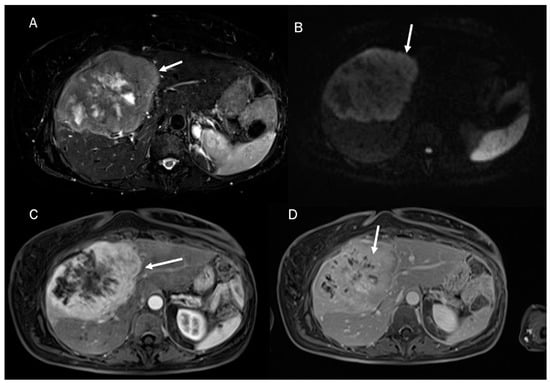

Figure 5.

ICC MRI assessment. The lesion (arrow) shows hypointense signal in T2-W sequence (A) due to fibrotic tissue, with targetoid appearance in DWI (B) and ADC map (C) and progressive contrast enhancement during arterial (D), portal (E), and delay (F) phases of contrast study.

In MRI imaging, ICC presents typical features as capsular retraction adjacent to the tumor. In T1-W sequences, the lesion appears with a targetoid aspect or hypointense signal. While most of the lesions also appear targetoid (Figure 5) in T2 sequences, some can show hyperintense signals. After contrast administration in the arterial phase in ICC, it is possible to identify the peripheral rim hyperenhanced. In the portal phase, the lesion slowly increases its entire enhancement (Figure 5 and Figure 6) [181,182,183,184].